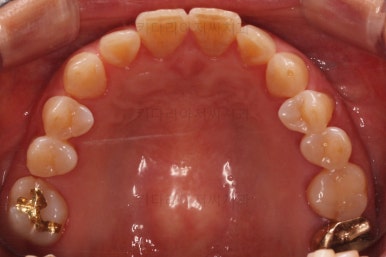

초진 때의 사진입니다.

제일 하단의 X-ray에서 문제점이 보이는데요.

해당 부분의 어금니 1개가 없었어요.

어금니가 없어진지 꽤 시간이 흘렀기 때문에 몇 가지 문제점이 나타나는데요.

치아가 없는 자리에 바로 임플란트가 불가능합니다.

치아를 뽑자마자 임플란트를 했다면, 치료는 간단했겠지만 이번의 경우는 시간이 오래 지나서 뒤쪽 어금니가 발치된 자리로 쓰러졌어요.

앞쪽 치열들도 발치된 자리로 조금씩 이동하는 바람에 틈새가 듬성듬성 생겼어요.

경우에 따라서는 맞물리는 치아(이번 환자분의 경우 아랫니)가 솟구쳐 오르면서 어금니 교합이 망가져요.